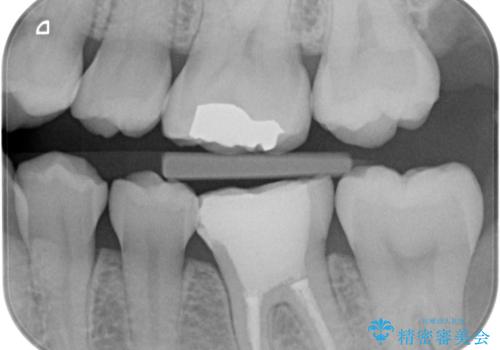

- 他院で根管治療を終えて被せ物を入れたいとの事で来院。

形を整えて型取りをし、ジルコニアクラウンを装着しました。